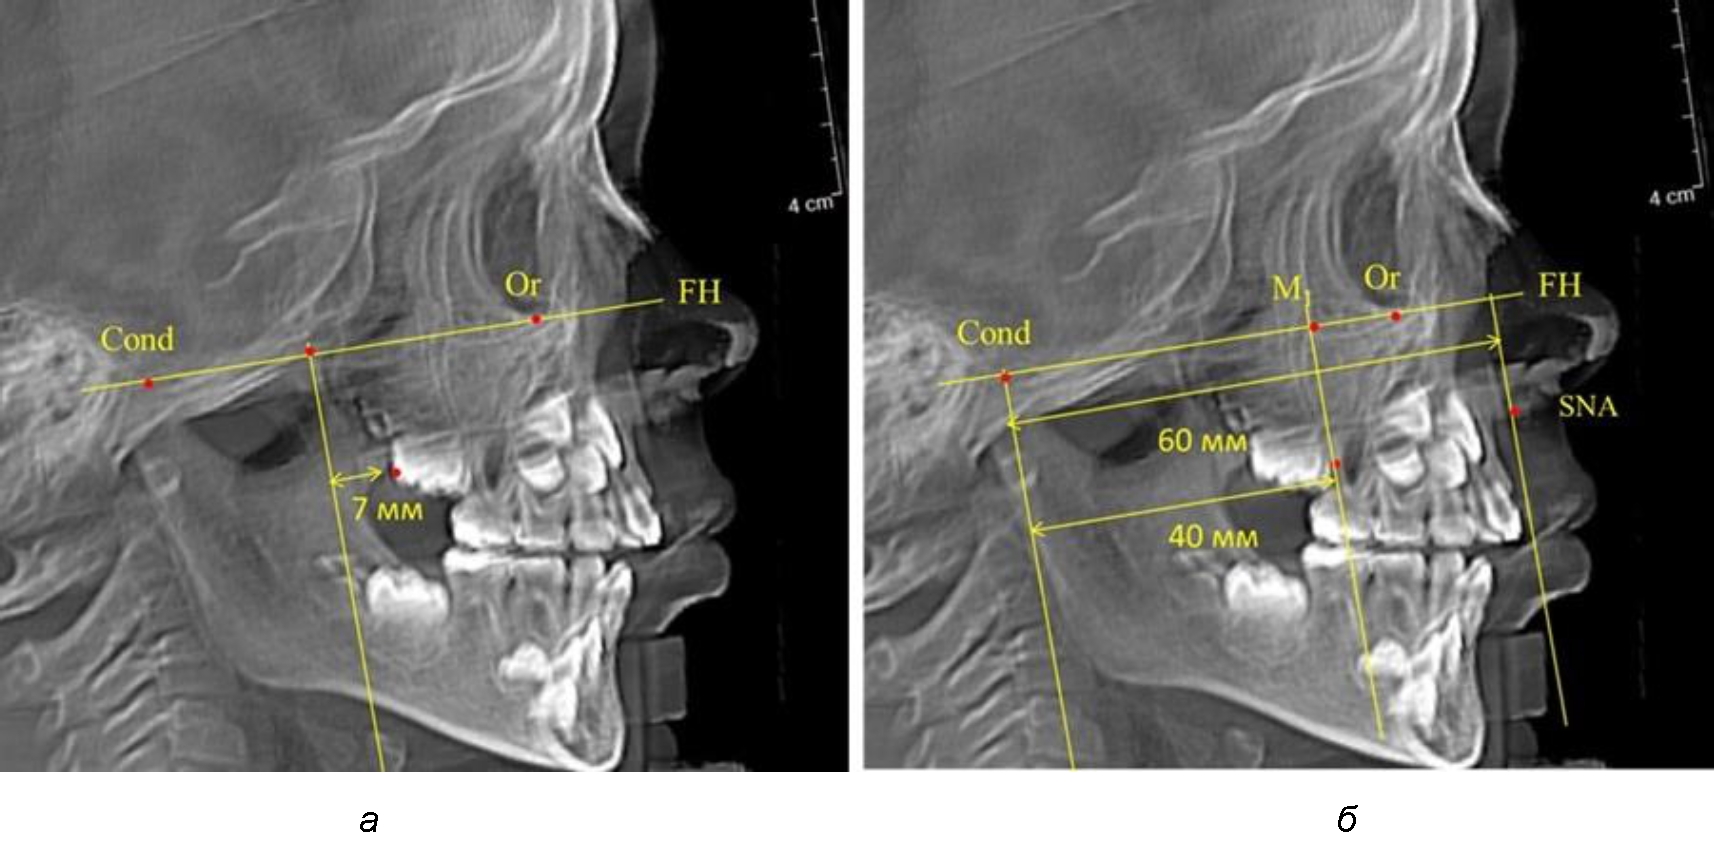

В то же время при увеличенном расстоянии от крыловидной вертикальной плоскости PTV до дистальной поверхности верхнего первого постоянного моляра, равное 23 мм, сагиттальный размер гнатического отдела составил 92 мм. При этом отношение кондилярно-спинального расстояния к кондилярно-молярному размеру (30,5), так же, как и при малых размерах, было близким к коэффициенту 1,5, что представлено на рис. 3.

Рис. 3. Особенности положения первых моляров по R. E. McDonald (а) и по предложенному методу (б) при увеличенном молярно-крыловидном расстоянии

Второй частью исследования был анализ положения первых постоянных моляров в различные периоды сменного прикуса. На телерентгенограммах детей периода прикуса молочных зубов дистальная поверхность зачатка первого постоянного моляра отстояла от крыловидной вертикали на величину, составляющую около 7 мм, что было близким по значению к данным R. E. McDonald. Сагиттальный размер гантического отдела составлял около 60 мм, а его отношение к кондилярно-молярной глубине – 1,5 (рис. 4).